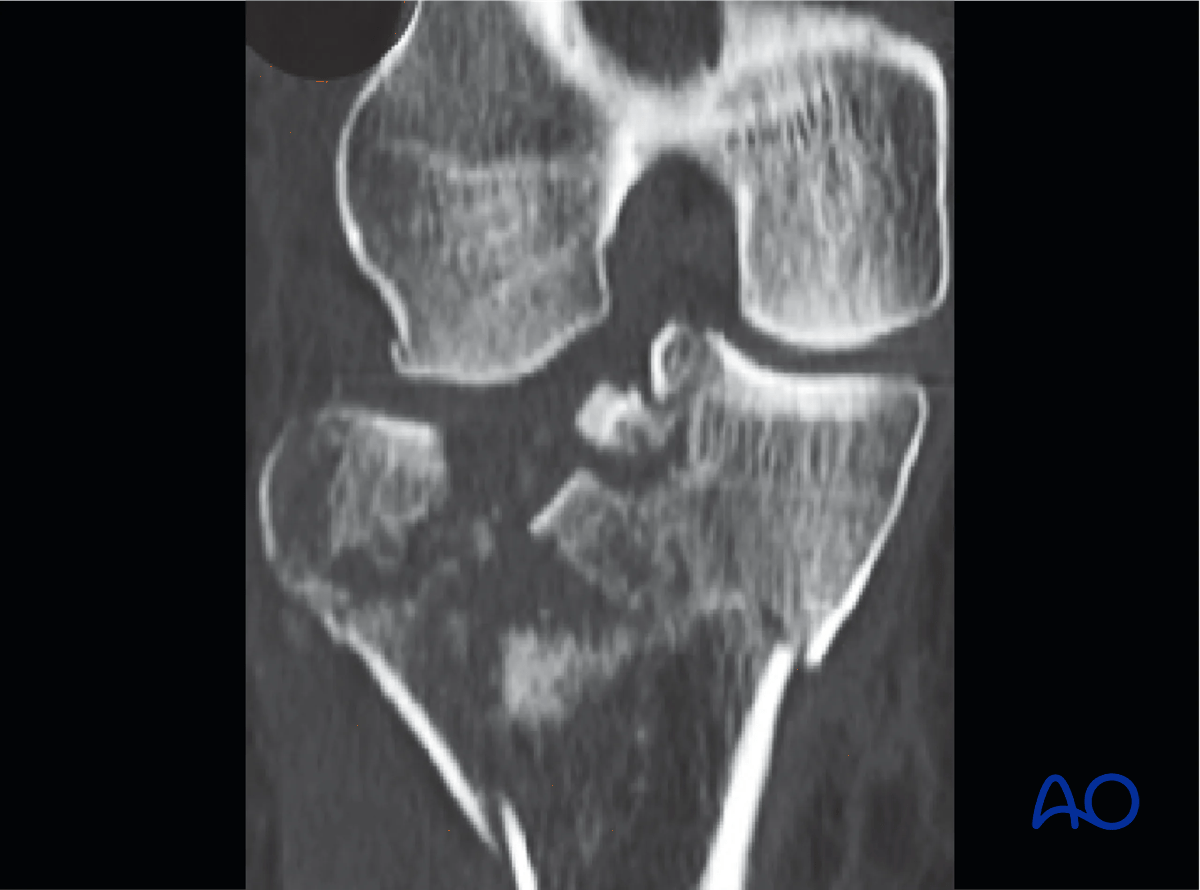

Coronal image showing simple medial condyle fracture and markedly depressed comminuted lateral plateau fracture.

Proximal tibia - Coronal image showing simple medial condyle fracture and markedly depressed comminuted lateral plateau fracture